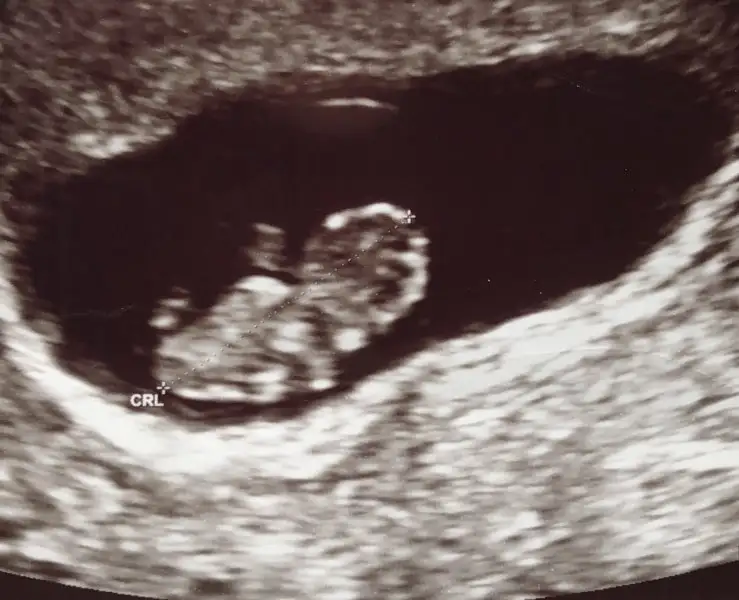

Eki Görüntüle 2124802

Günaydın kızlarr tahmin alayım ozaman sizden cinsiyet için :))